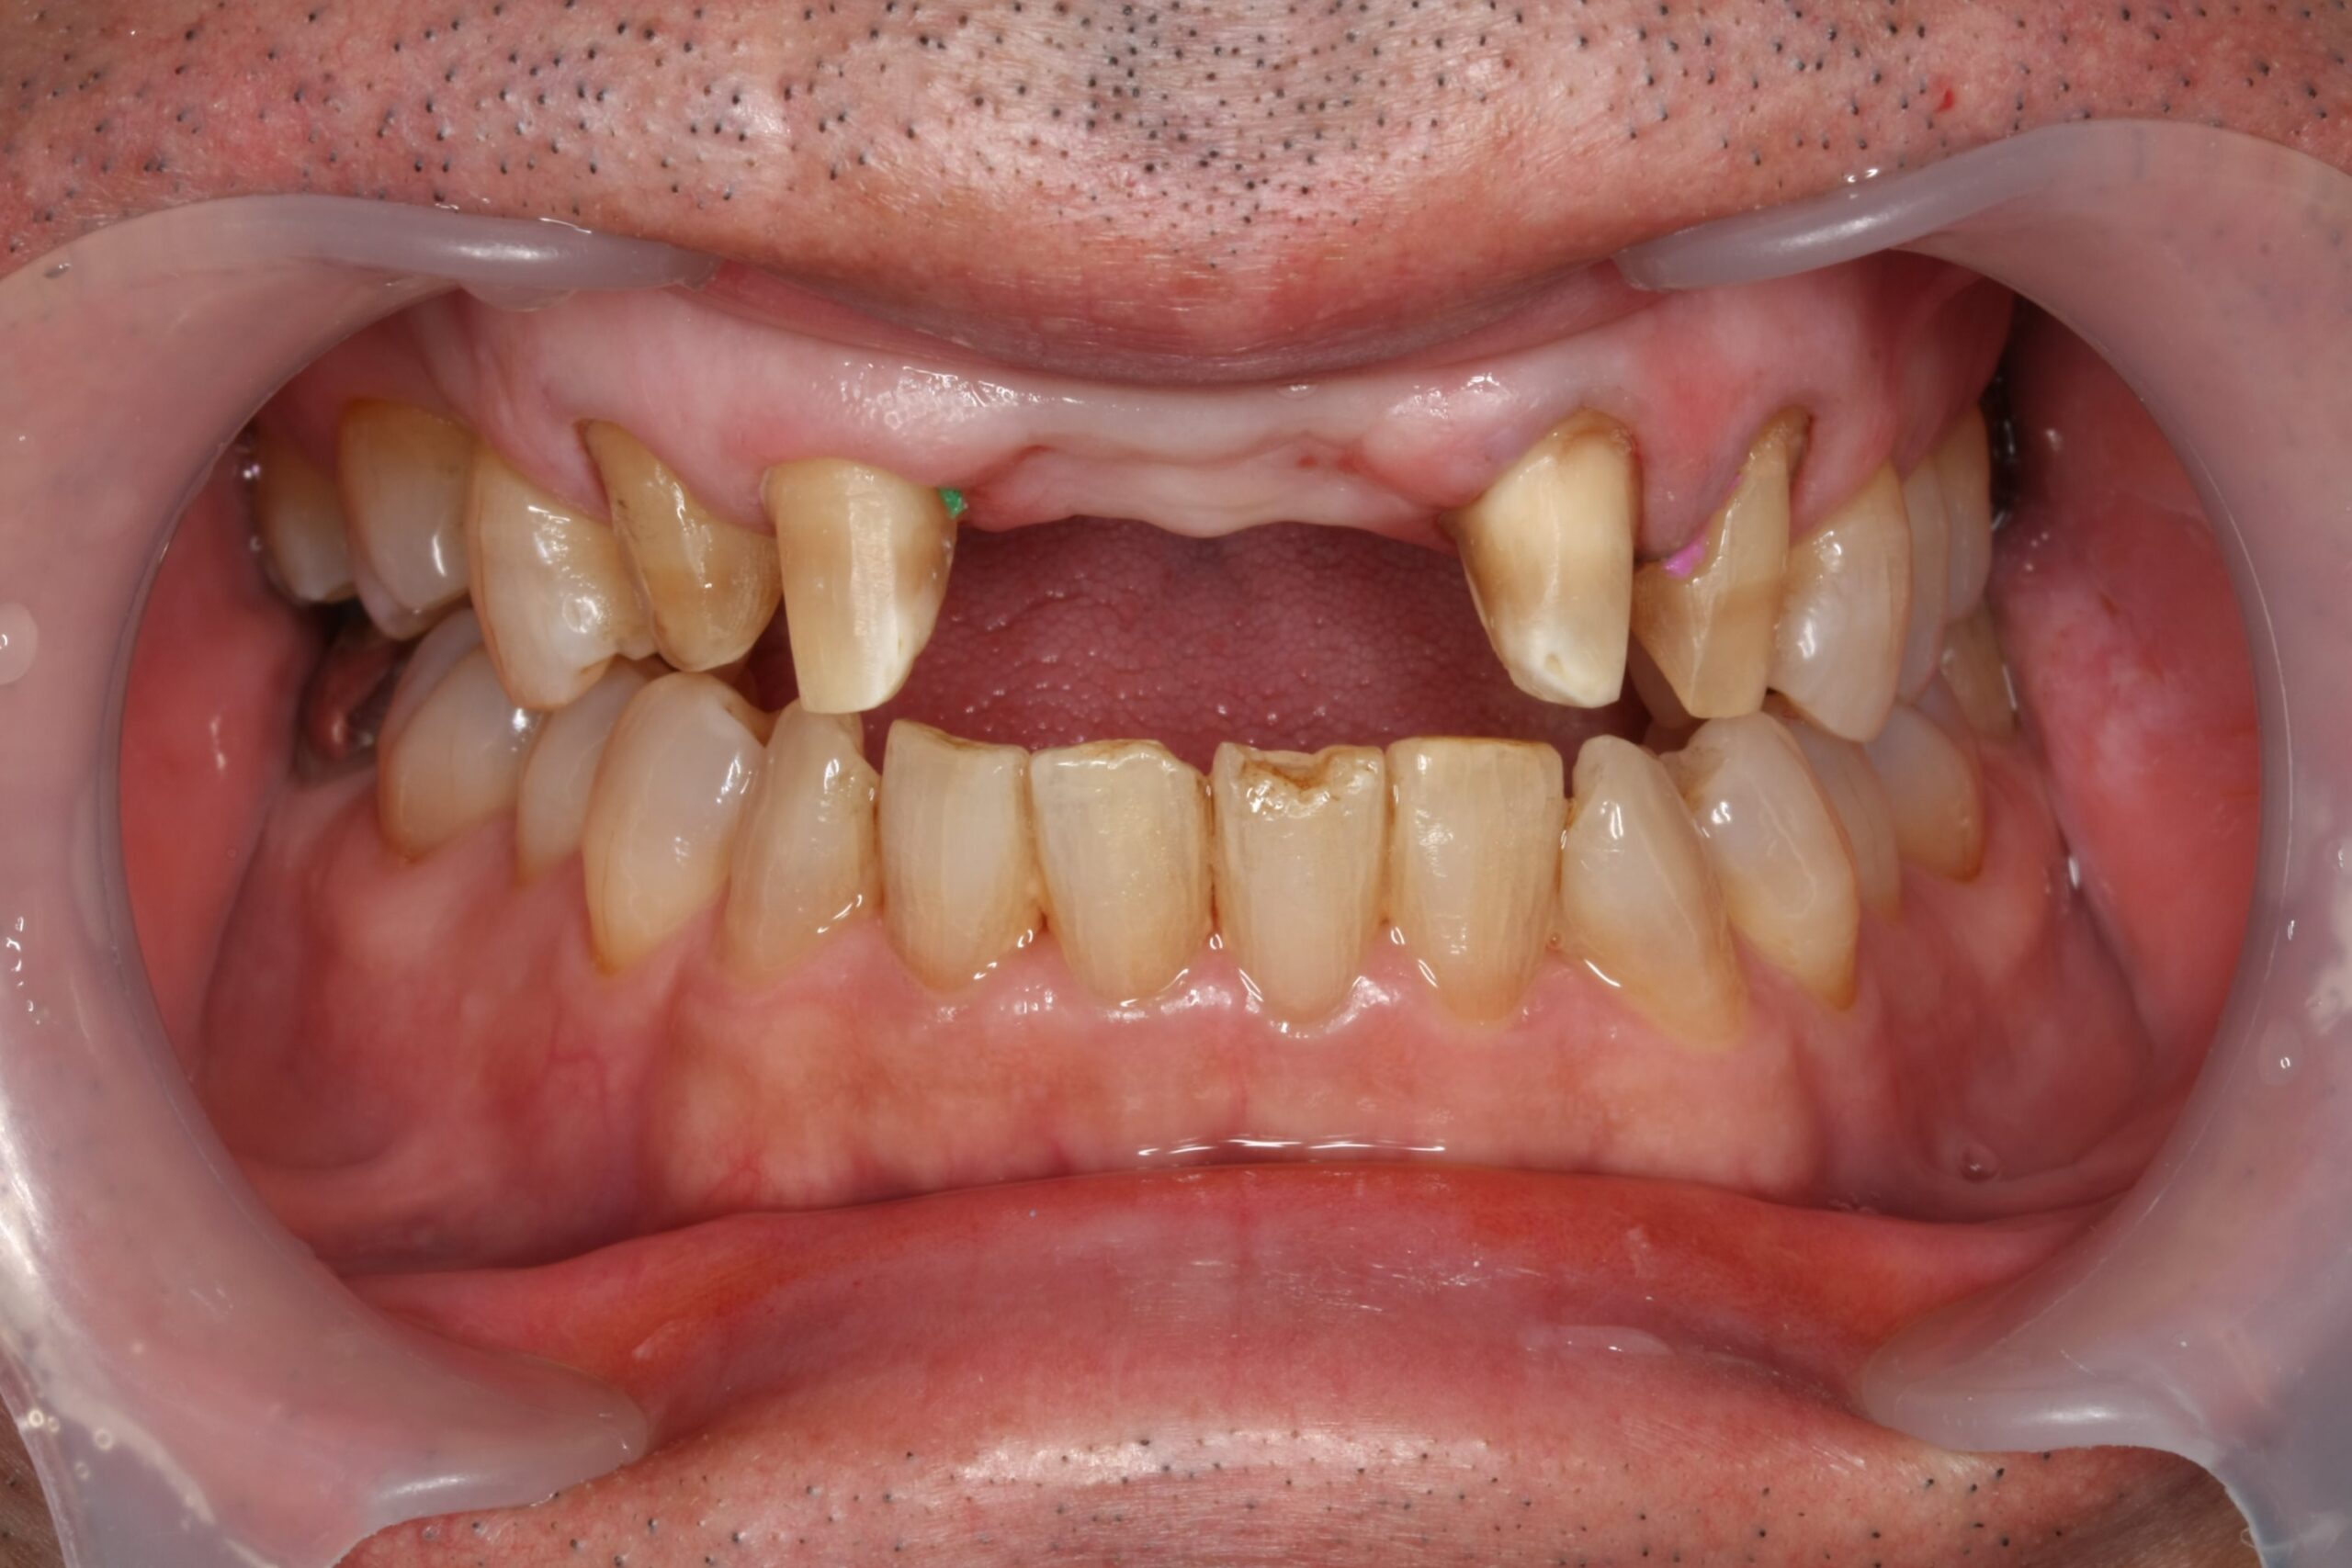

抜歯後3ヶ月

抜歯後は、歯ぐきや骨の形が時間とともに変化します。

そのため、すぐに最終的なブリッジを作製せず、治癒を待ちながら経過を確認しました。